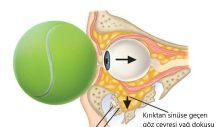

Yaşlanma, daha önce geçirilmiş fıtık, mesleki zorlanmalar, kireçlenmeler ve eski ameliyatlara bağlı bel problemi olanlarda stres durumu daha da olumsuz hale getirir. Önceden yatkınlığı olanlarda hafif bir kas gerginliği bile ciddi omurga (bel-boyun-sırt) ağrılarına yol açar. Kireçlenmeler ya da daha önceki nedenlerden dolayı omurgada hareket kısıtlılığı olanlarda kas gerginlikleri sinirleri sıkıştırır ve siyatalji (bacak ağrısı), brakiyalji (omuz ve kol ağrısı) gibi belirtileri alevlendirir. Gergin bel kasları, bel ağrısını arttırır. Ve ağrı kaslardaki gerginliği artırır. Her şekilde ağrı-bel ağrısı-ağrı arasında kısır bir döngü oluşur.